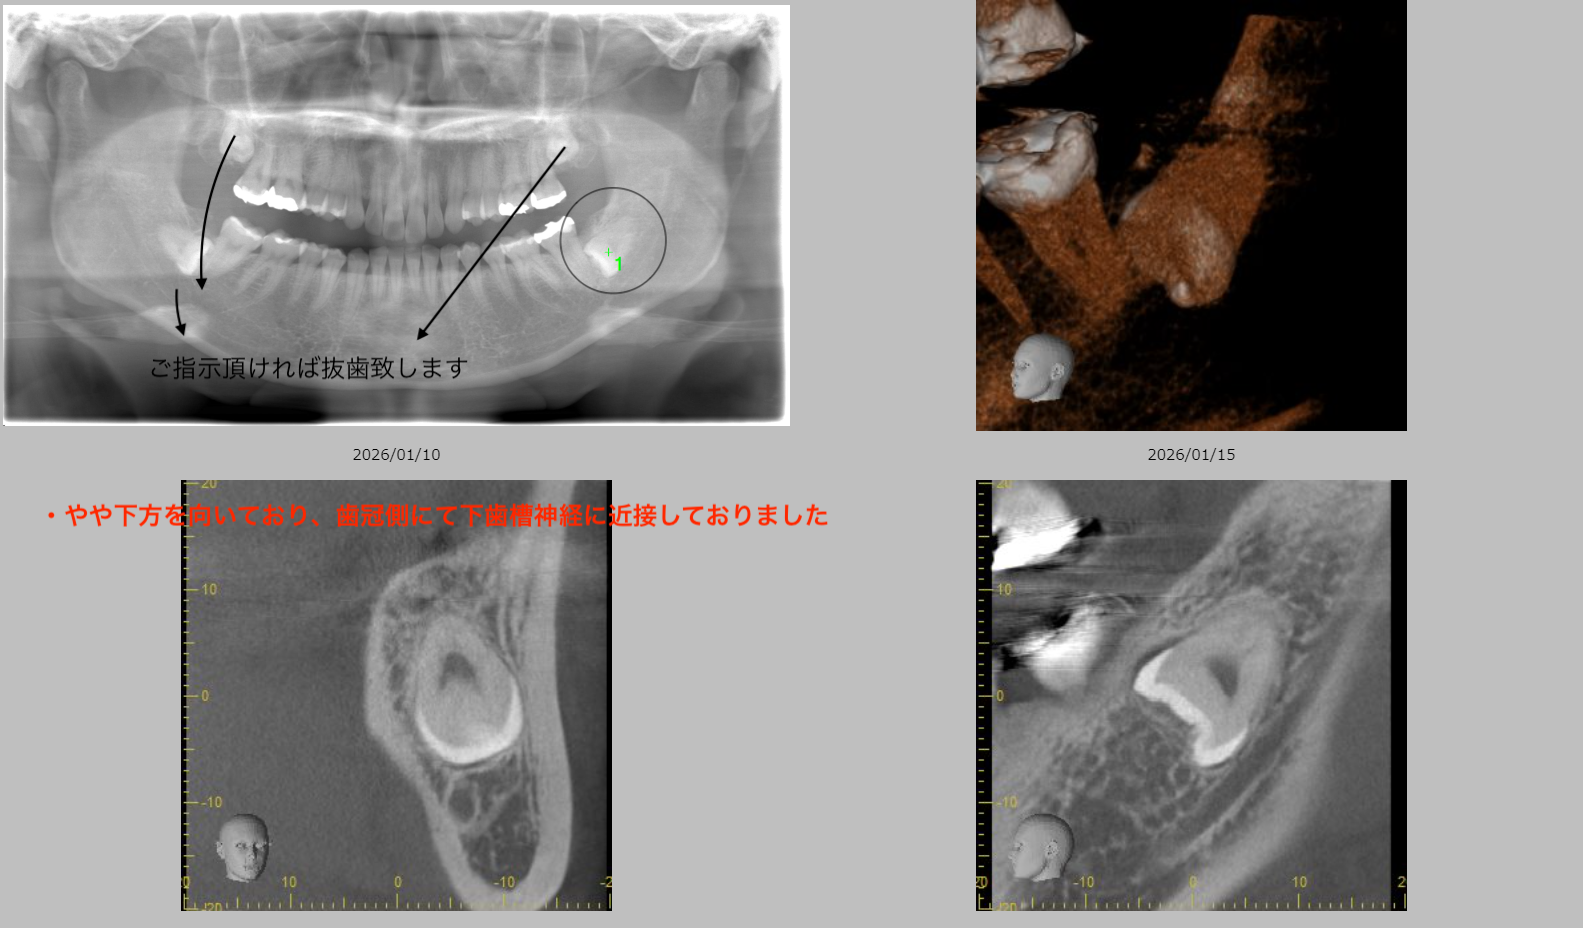

書面・フィードバックのサンプル

「経過が把握できる」紹介を心がけています